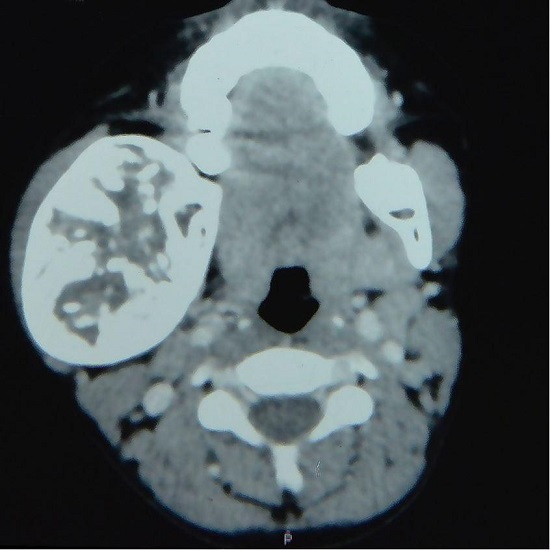

A 5-year-old girl was reported to the Head and Neck Surgery Department with the complaint of progressive right facial swelling over the last 2 years that reached the size of 7 × 6 cm at the initial evaluation. The mass involved the right side of the mandible with regular margins, but did not reduce the mouth opening. A contrast-enhanced computed tomography (CT) showed a 6.5 × 6 × 4.5 cm lytic lesion involving the right ramus and body of the mandible (Figure 1).